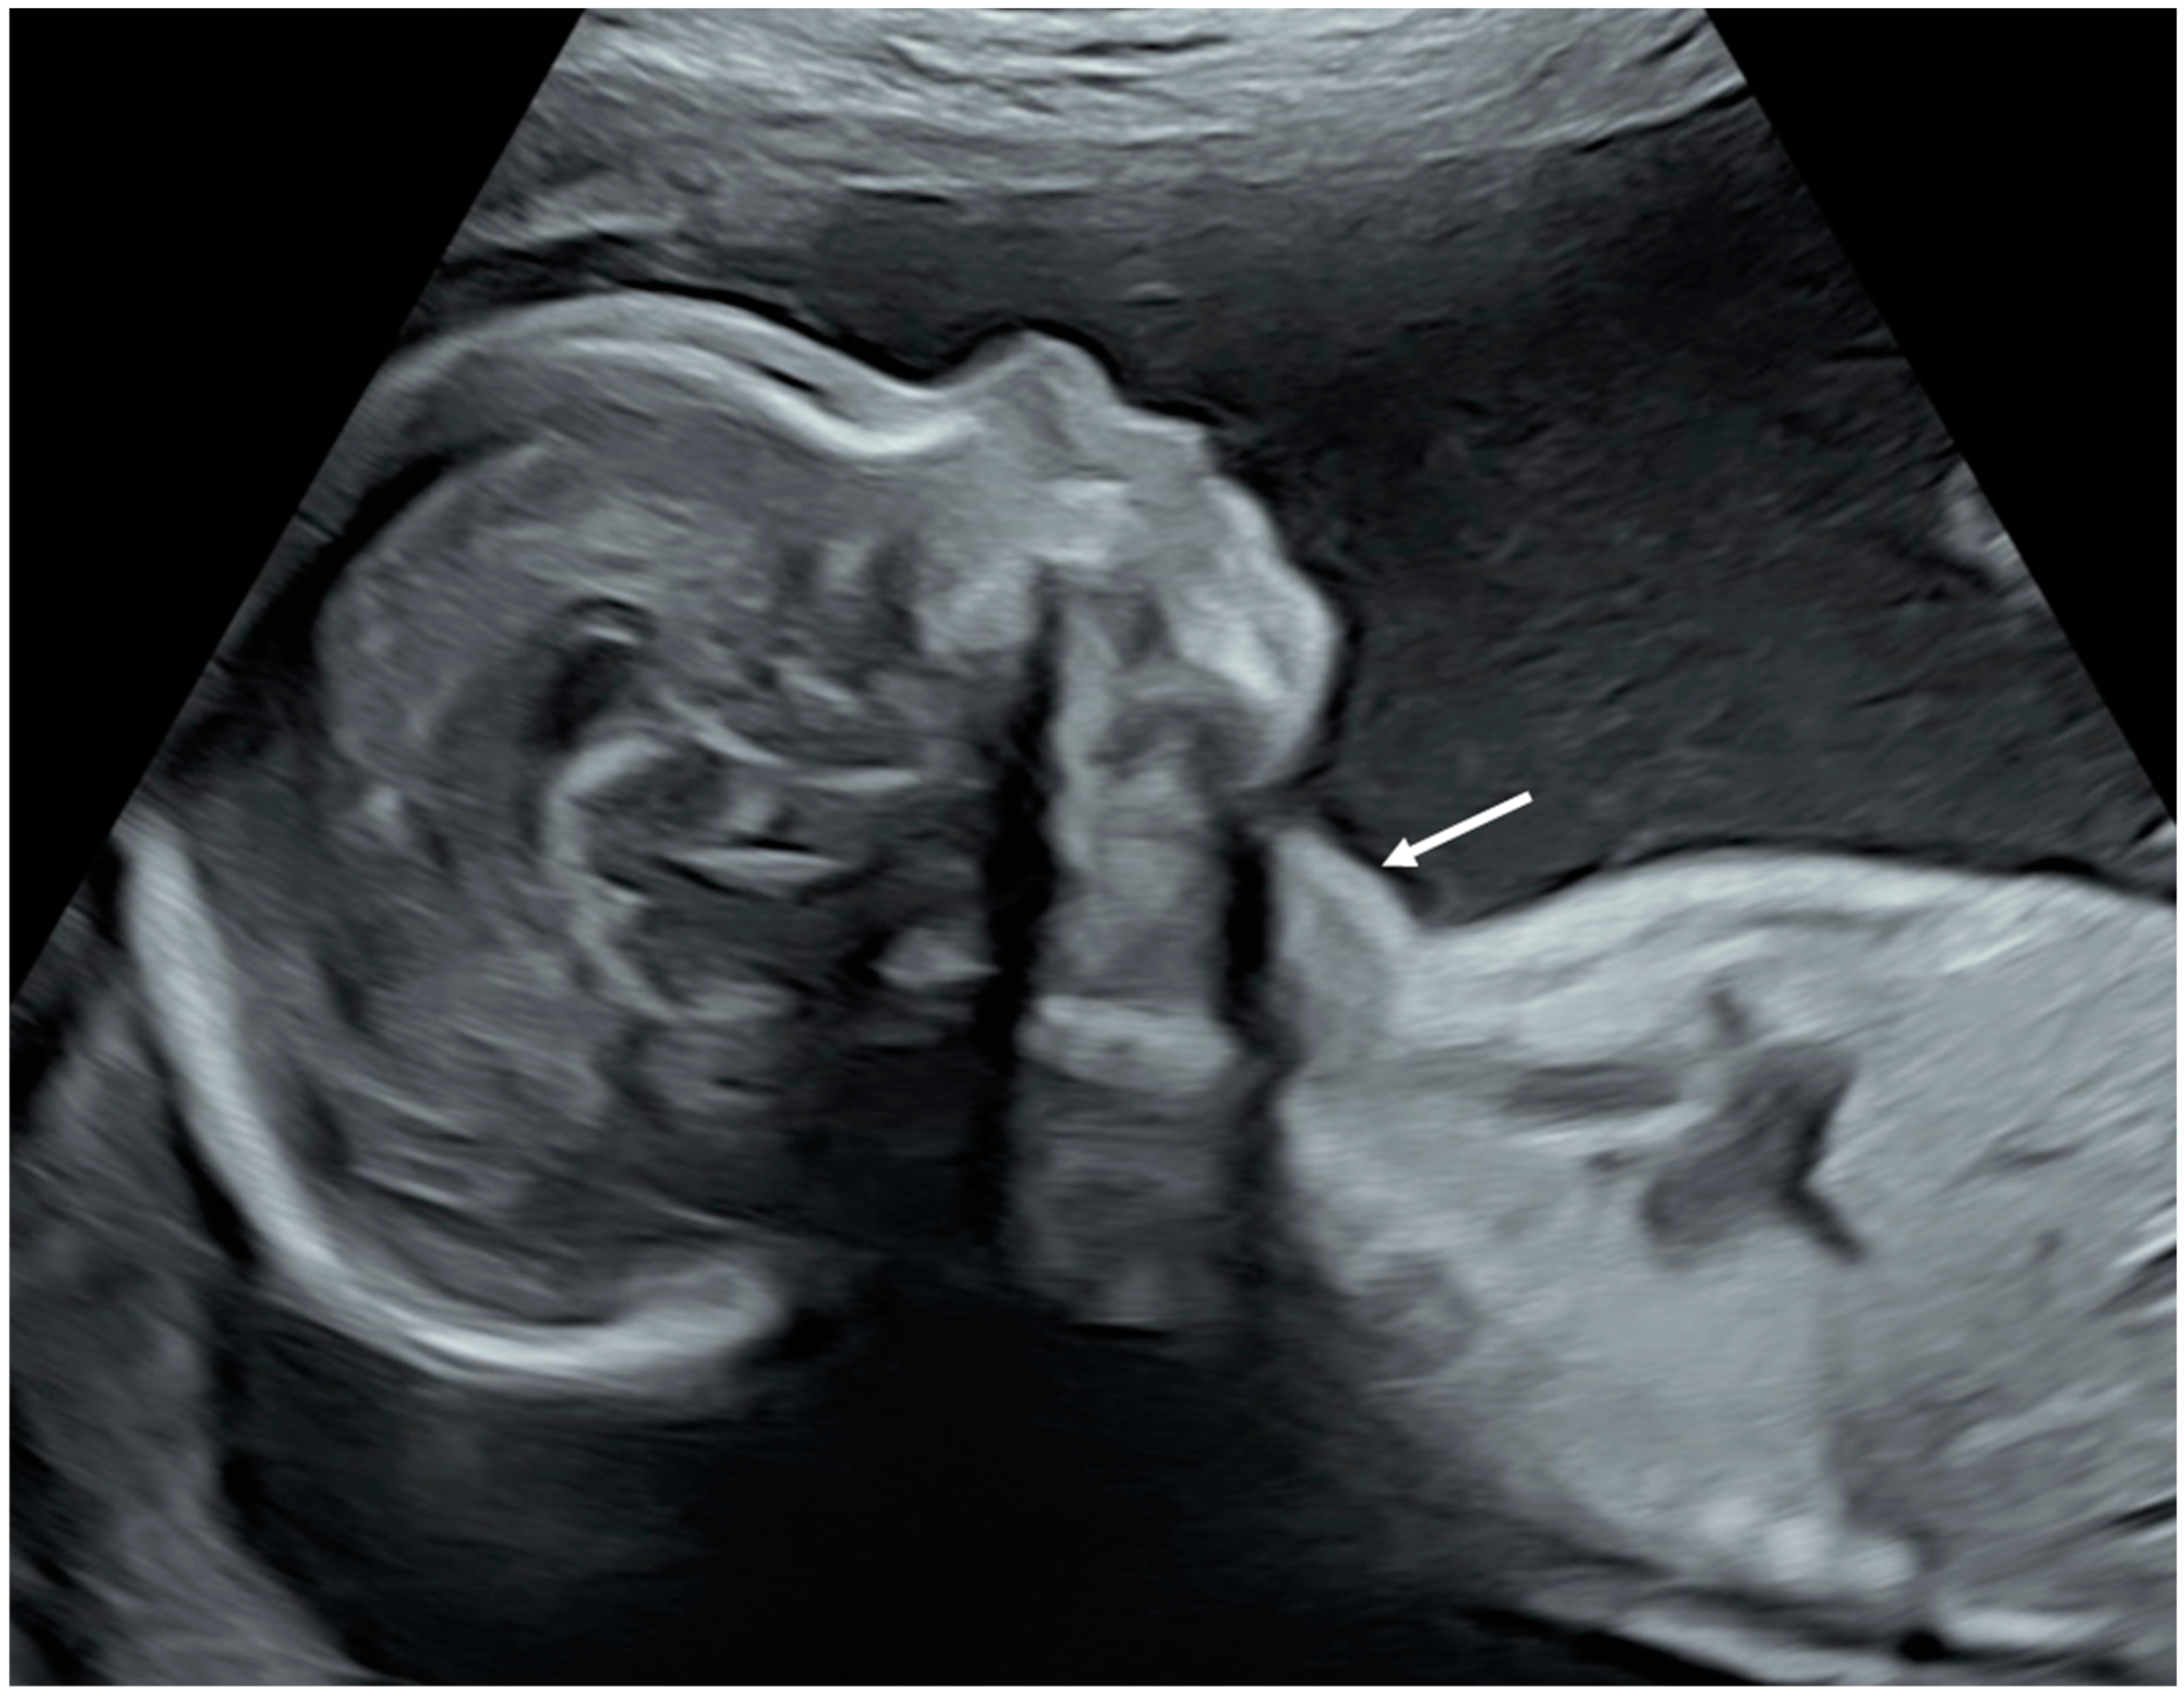

- Huel, C.; Guibourdenche, J.; Vuillard, E.; Ouahba, J.; Piketty, M.; Oury, J.F.; Luton, D. Use of ultrasound to distinguish between fetal hyperthyroidism and hypothyroidism on discovery of a goiter. Ultrasound Obstet. Gynecol. 2009, 33, 412–420. [Google Scholar] [CrossRef]

- Ranzini, A.C.; Ananth, C.V.; Smulian, J.C.; Kung, M.; Limbachia, A.; Vintzileos, A.M. Ultrasonography of the fetal thyroid: Nomograms based on biparietal diameter and gestational age. J. Ultrasound Med. 2001, 20, 613–617. [Google Scholar] [CrossRef]

- Luton, D.; Le Gac, I.; Vuillard, E.; Castanet, M.; Guibourdenche, J.; Noel, M.; Toubert, M.E.; Léger, J.; Boissinot, C.; Schlageter, M.H.; et al. Management of Graves’ Disease during Pregnancy: The Key Role of Fetal Thyroid Gland Monitoring. J. Clin. Endocrinol. Metab. 2005, 90, 6093–6098. [Google Scholar] [CrossRef] [PubMed]